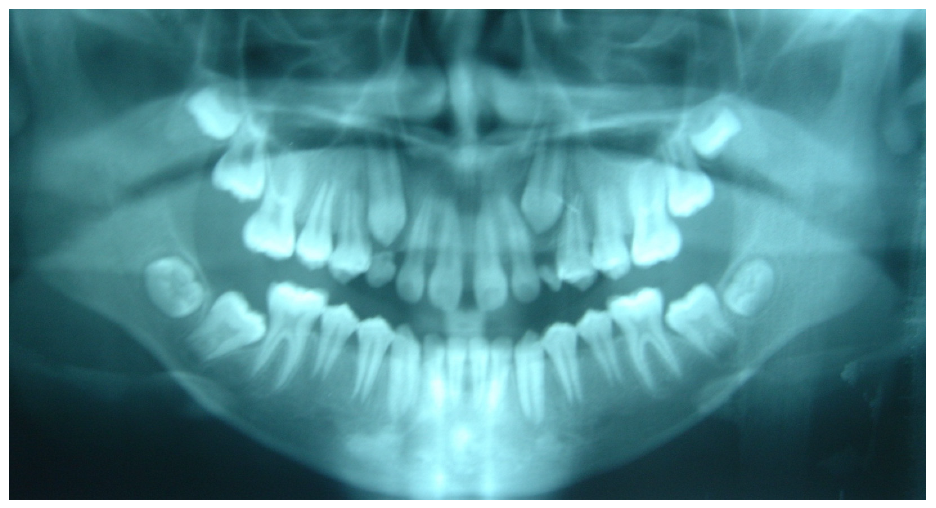

| Chinese-Americans | 151 | 73 | 78 | 90 | 61 | 212 |